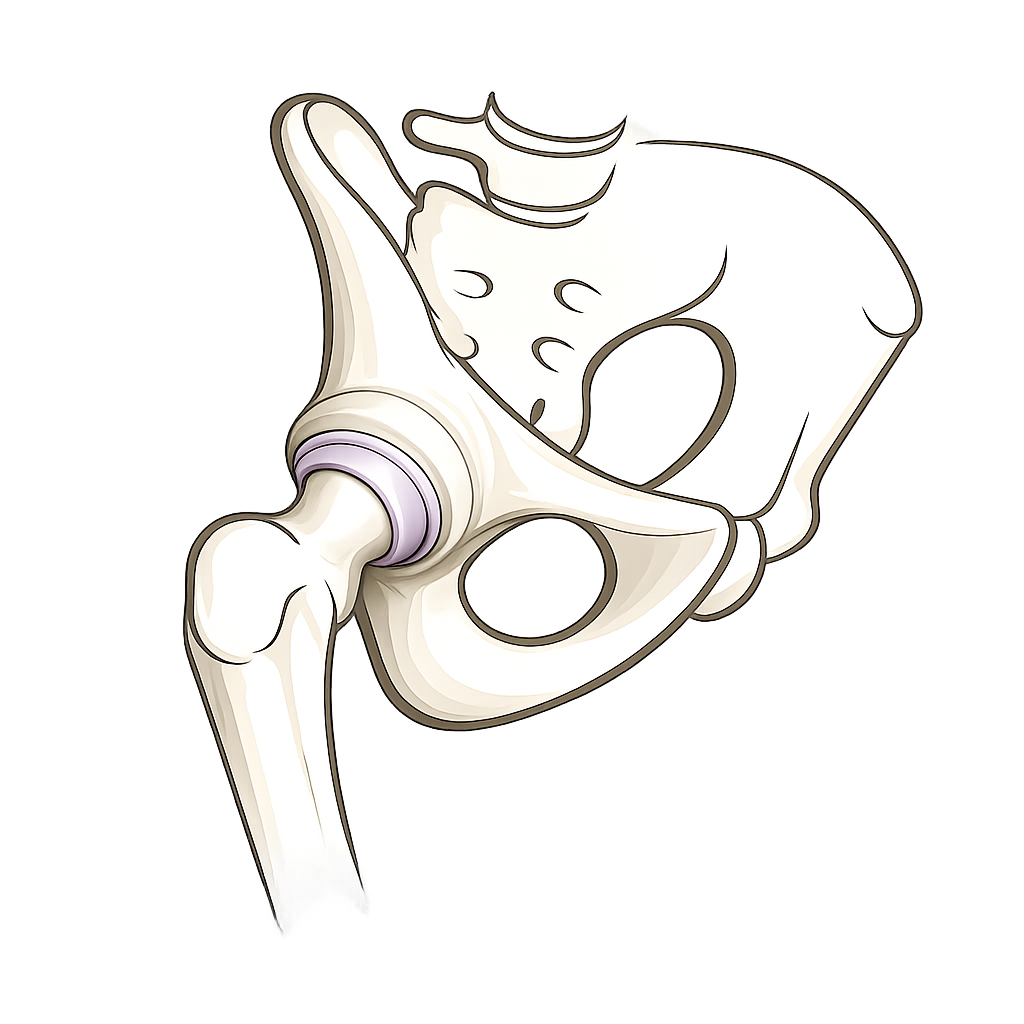

PD Dr. Rahm zählt national zu den ersten Anwendern des Keramik-Keramik Hip Resurfacing. Die innovative Prothese deckt lediglich die Oberfläche von Hüftkopf und Pfanne mit einer Keramikoberfläche ab.

Aufgrund der Beschaffenheit des Materials entsteht praktisch kein Materialabrieb, was sich sehr günstig auf die Langlebigkeit der Prothese auswirkt. Insbesondere für sportliche Patienten ist dies ein Lichtblick für die operative Behandlung einer Hüftarthrose.

PD Dr. Rahm wird ausführlich die Vor- und Nachteile dieser neuen Prothesenart vorstellen – oder gibt es sogar gar keine Nachteile mehr?